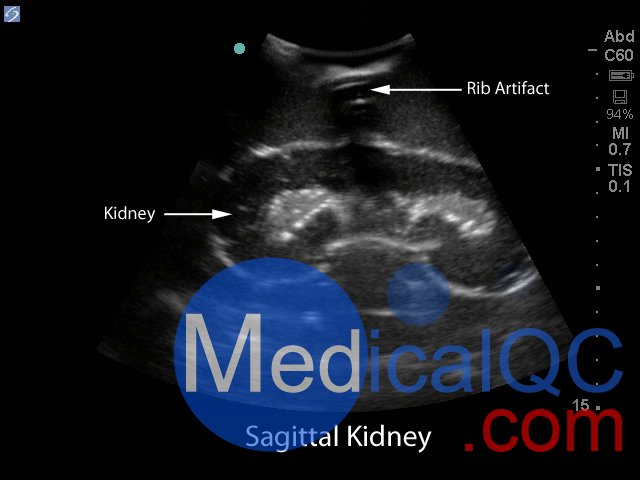

Blue Phantom的經(jīng)皮腎穿刺活檢超聲訓(xùn)練模型允許使用芯針穿刺活檢或穿刺穿刺技術(shù)重復(fù)進(jìn)行針頭活檢。該模型提供了解剖學(xué)上正確的成年男性軀干,其超聲組織模塊包含皮膚,肋骨和右腎以及周圍組織。腎臟的內(nèi)部和外部結(jié)構(gòu)在其逼真度和成像特性方面極佳,并且包含腎皮質(zhì),腎髓質(zhì)以及主要和次要的花萼。使用與真實(shí)人體組織的聲學(xué)特征相匹配的Blue Phantom模擬組織構(gòu)造而成,因此,當(dāng)您在我們的訓(xùn)練模型上使用超聲系統(tǒng)時(shí),您將獲得與在臨床環(huán)境中對(duì)患者進(jìn)行成像所期望的相同質(zhì)量。

超聲成像和程序技能包括;使用超聲系統(tǒng)控制,換能器定位和移動(dòng),識(shí)別腎解剖結(jié)構(gòu),在腎活檢期間避免肋骨出現(xiàn),避免肋骨出現(xiàn),使用超聲將目標(biāo)對(duì)準(zhǔn)腎活檢的適當(dāng)位置并執(zhí)行超聲引導(dǎo)的腎活檢程序。使用配置了適當(dāng)?shù)哪I臟活檢換能器的任何超聲成像系統(tǒng),此超聲動(dòng)手訓(xùn)練模型將表現(xiàn)良好。這種超聲體模模型非常適合包括腎臟科,介入放射學(xué),外科手術(shù),外科手術(shù)訓(xùn)練計(jì)劃,超聲訓(xùn)練計(jì)劃,模擬中心,外科技能中心,醫(yī)學(xué)教育設(shè)施,腎臟活檢設(shè)備制造商和超聲制造商進(jìn)行超聲教育和演示的專業(yè)。

具有包含皮膚,肋骨和右腎以及周圍組織的超聲組織模塊,解剖學(xué)上正確的成年男性軀干

腎臟的內(nèi)部和外部結(jié)構(gòu)在其逼真度和成像特性方面極佳,并且包含腎皮質(zhì),腎髓質(zhì)以及主要和次要的花萼